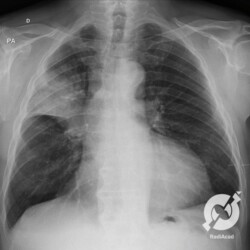

E o nome dado a esta alteração radiográfica que corresponde à substituição do ar alveolar por líquido é a consolidação alveolar.

Uma consolidação alveolar é, por definição, uma opacidade (imagem densa, branquinha) homogênea ou às vezes heterogênea (pela presença de calcificações ou cavidades), de limites mal definidos, exceto quando toca a pleura da parede ou das cissuras pulmonares. É um termo usado tanto em radiografia, como em tomografia computadorizada. Na tomografia, um outro termo é usado: vidro fosco, que é uma opacidade (branquinha mas não tanto como a consolidação), que borra o pulmão mas deixa ver os vasos de permeio (igual bigode de adolescente: dá pra ver todo o fundo).

Nós vamos mostrar aqui um pequeno apanhado de pneumonias de variados agentes, em diversos segmentos e lobos pulmonares, com extensões variadas. O objetivo é identificar o padrão radiológico de consolidação alveolar e não determinar o agente infeccioso, isso vai ser assunto para mais adiante. Aliás já antecipo que é fundamental saber localizar a lesão, porque alguns destes bichos gostam de determinados segmentos, alguns tumores também têm as suas preferências, então localização é fundamental. Se localização não fosse importante, um apartamento na beira do mar sairia o mesmo preço de um apartamento de frente pra BR-101, concordam?

Seguem alguns dos nossos casos de pneumonia para vocês treinarem os olhos e não se apavorarem nos plantões.